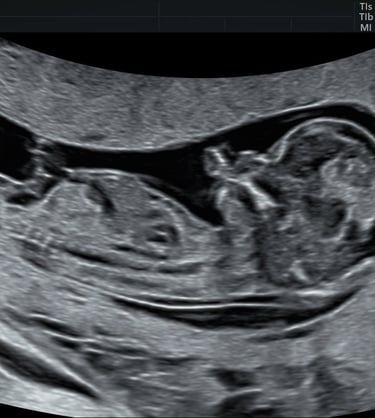

Lors d’une grossesse, l’échographie est un outil indispensable pour le suivi.

Il s’agit d’un examen de dépistage et non d’un diagnostic.